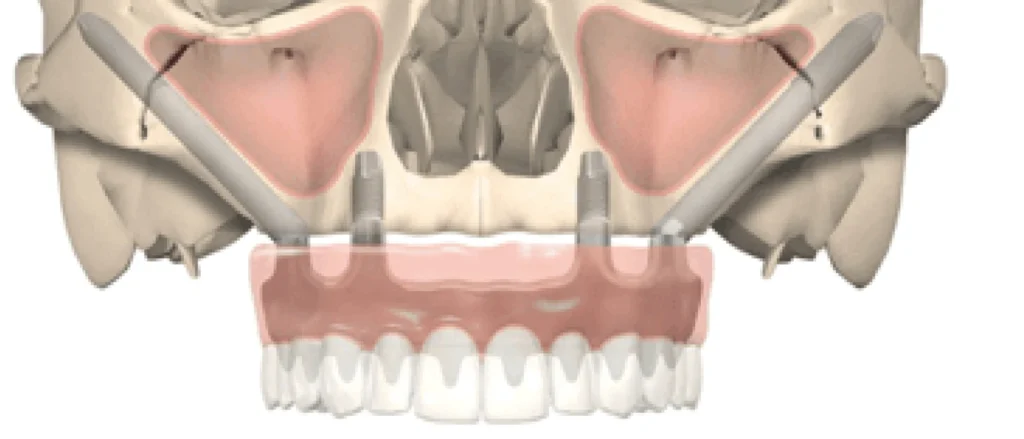

Si l’atrophie osseuse concerne toute la mâchoire, 4 implants zygomatiques sont nécessaires. Ils sont placés de manière à sortir sous les incisives latérales et les 2 ème prémolaires. L’implant supérieur longe à distance du rebord orbitaire, l’implant inférieur chemine sur la plus grande longueur d’ancrage osseux quelques millimètres plus bas. Le nerf infra-orbitaire responsable de la sensibilité para-nasale et jugale doit être respecté lors de la pose implantaire au risque de trouble de la sensibilité. On parle de réhabilitation prothétique fixe sur 4 implants zygomatiques ou quad zygomatiques.

L’émergence implantaire des implants zygomatiques a tendance à être plus palatine que les implants axiaux droits au vue de l’axe d’insertion des implants dans le zygoma malgrè l’angulation à 55 degrés du col implantaire. La conséquence est un élargissement prothétique en palatin pour englober les puits de vissage de la prothèse à transvisser dans le pilier. Malgrè cet sur épaisseur en palatin il n’y aura jamais de faux-palais. Les prothèses sont réalisés en Zircone (Céramique) pour un meilleur rendu esthétique et résistance mécanique. Dans les cas d’atrophies extrêmes, le défaut de hauteur osseuse est compensé par une hauteur prothétique importante habillée avec de la fausse gencive.

Sous anesthésie générale ou locale, nous plaçons les implants avec précision grâce à un guide chirurgical en titane. Un bridge en zircone, préparé avant l’opération, est fixé sur les implants. Les patients se réveillent avec de nouvelles dents.